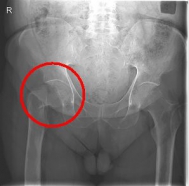

In addition to a thorough physical examination, radiographs of the pelvis and the affected hip are crucial for the diagnosis.

Images: Here is the supply of a dynamic hip screw shown.